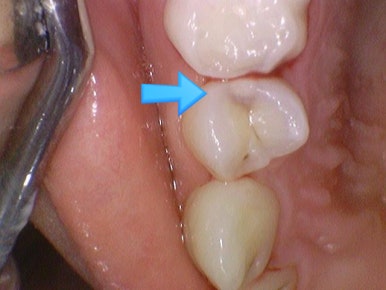

충치가 있다고 진단받았으나 겉에서 보이지 않는다고 방치하여

깨져서 온 사례

환자분은 치아사진을 보면 치아가 썩은 것처럼 보이지 않는다면서(화살표 부분)

방치하다가 6개월이 지난 후 치아가 깨져서 오게 되었습니다.

x-ray를 통해 충치가 있다고 진단받은 치아 6개월 후 파절되어 오심

결국 6개월 후에는 치아가 깨졌다며 오셨습니다.

치아 대부분이 무른 충치이고, 단단한 부분은 껍질처럼 얇게 남아있었기 때문에 치아가 쉽게 깨지게 됩니다.

물론 신경치료+크라운을 시도해보겠지만

결국 오셨을 때는 치아가 예전보다 너무 많이 파절되어 크라운도 하기 힘들 수도 있습니다.

발치 가능성이 예전보다 더 높아진 상태로 오셨습니다.